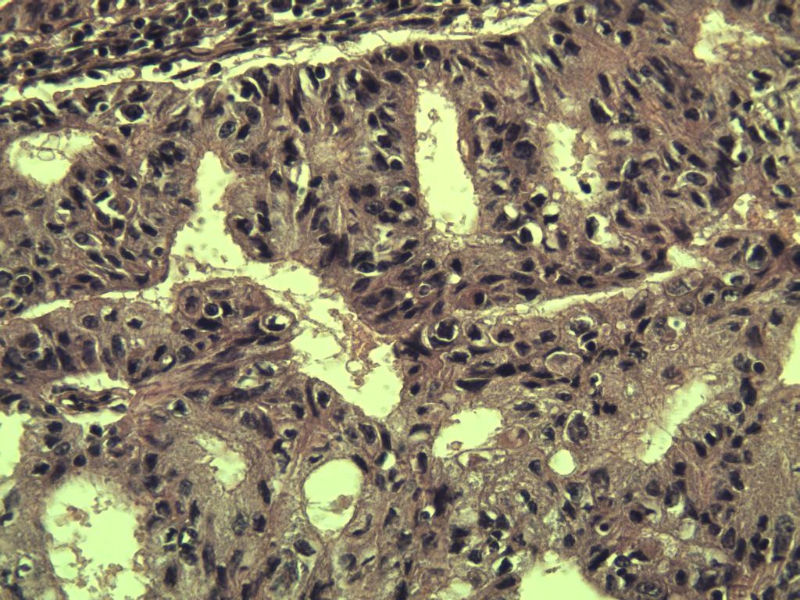

名称:图4

描述:a147.Jpg.jpg